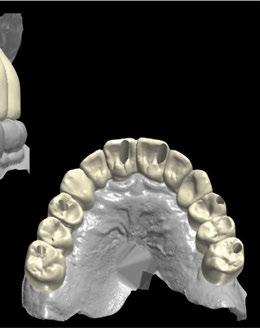

-Escáner intraoral mediante iTero Element™2 con el fin de obtener modelos digitales (archivos STL) (Figura 3).

Figura 3. Archivo STL inicial obtenido mediante iTero Element™2.

1. Planificación digital y diseño de la férula de cirugía guiada Tras analizar el caso y siguiendo los parámetros estéticos y funcionales, se realizó un encerado digital de la arcada superior mediante el programa de diseño 3D Exocad® (Figura 5), el cual se imprimió y validó junto al paciente mediante un mock-up (Figura 6 a-b).

A continuación, para la planificación de los implantes dentales y el diseño de la férula de cirugía guiada se usó la plataforma digital RealGUIDE®. Para ello se realizó el matching, por un lado, del archivo STL del encerado digital; y, por otro, del archivo 3D. De esta manera, se pudo analizar el tejido óseo residual apical a cada diente y la posición de la raíz respecto a las corticales vestibular y palatina. También se estudió la relación de los contornos óseos con los tejidos blandos y con la posición final de los márgenes cervicales de la restauración protésica, pudiendo así planificar la posición 3D correcta de los implantes. En esta primera fase se diseñó una férula quirúrgica para la elevación de seno bilateral a partir del software RealGUIDE™, que nos sirvió de guía para el diseño de las ventanas de acceso. Esta férula se imprimió con la impresora 3D Formlabs® (Figura 7)